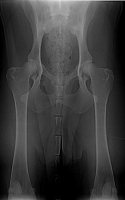

Znovu na rentgenu jsme byli ve zhruba čtyřech letech, kdy Grif prodělal amputaci plovací blány, protože se mu po zánětu udělala boule velikosti velkého vlašského ořechu. Rentgen, který zde vidíte je poslední, ze skoro sedmi let, kdy jsme byli na operaci s předním loktem, artrózu bylo nutné odfrézovat. Ano, to byla poslední zatím neoperovaná noha. Pro přehled je vedle další rentgen zdravého psa (mladého leonbergera). Prohlédněte si oba klouby. (Kliknutím otevřete obrázky v plné velikosti).